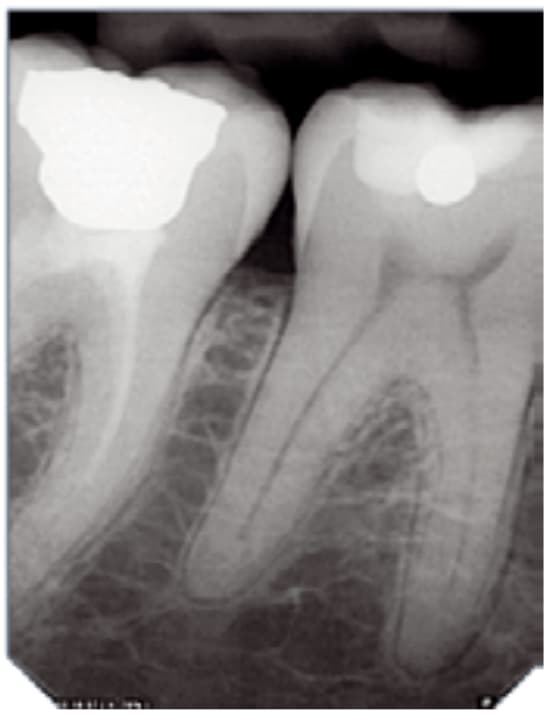

Wysoka rozdzielczość zapewnia dokładną i niezawodną diagnostykę. Technologia wielowarstwowa zapewnia obrazy o niskim poziomie szumów i z wyjątkową ostrością – w zaledwie kilka sekund.